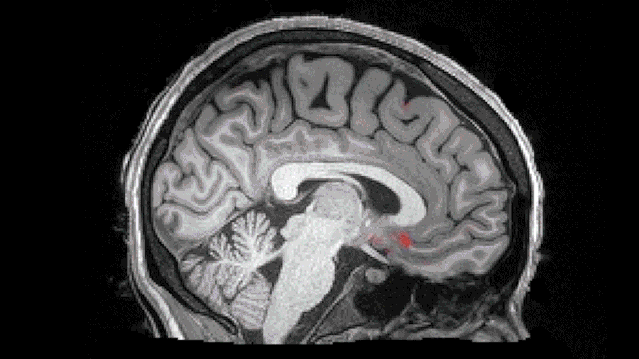

PNAS:熬夜导致海马体中抑制神经元活动增加,破坏记忆巩固

脑脊液反复清洗大脑的过程(DOI: 10.1126/science.aax5440)

不仅如此,熬夜导致的睡眠不足,除了为多年后的阿尔茨海默症“打下基础”之外,还会干扰海马体依赖性记忆,加重大脑负担,直接表现为记忆力减退。正如美国密歇根大学的研究学者在《美国国家科学院院刊》上发表的一项研究所述:

换句话说,熬夜诱发的睡眠不足,增加了海马体中抑制神经元活动,使得与存储记忆相关的海马体中正常神经元活动无法聚集,破坏了记忆的长期存储,扰乱学习后的记忆形成。

综上,熬夜使得阿尔茨海默症相关的β-淀粉样蛋白在脑内积聚,破坏学习后的记忆形成。如果不想卷了(unjuanable),试图早点“退休”,就去熬夜吧!